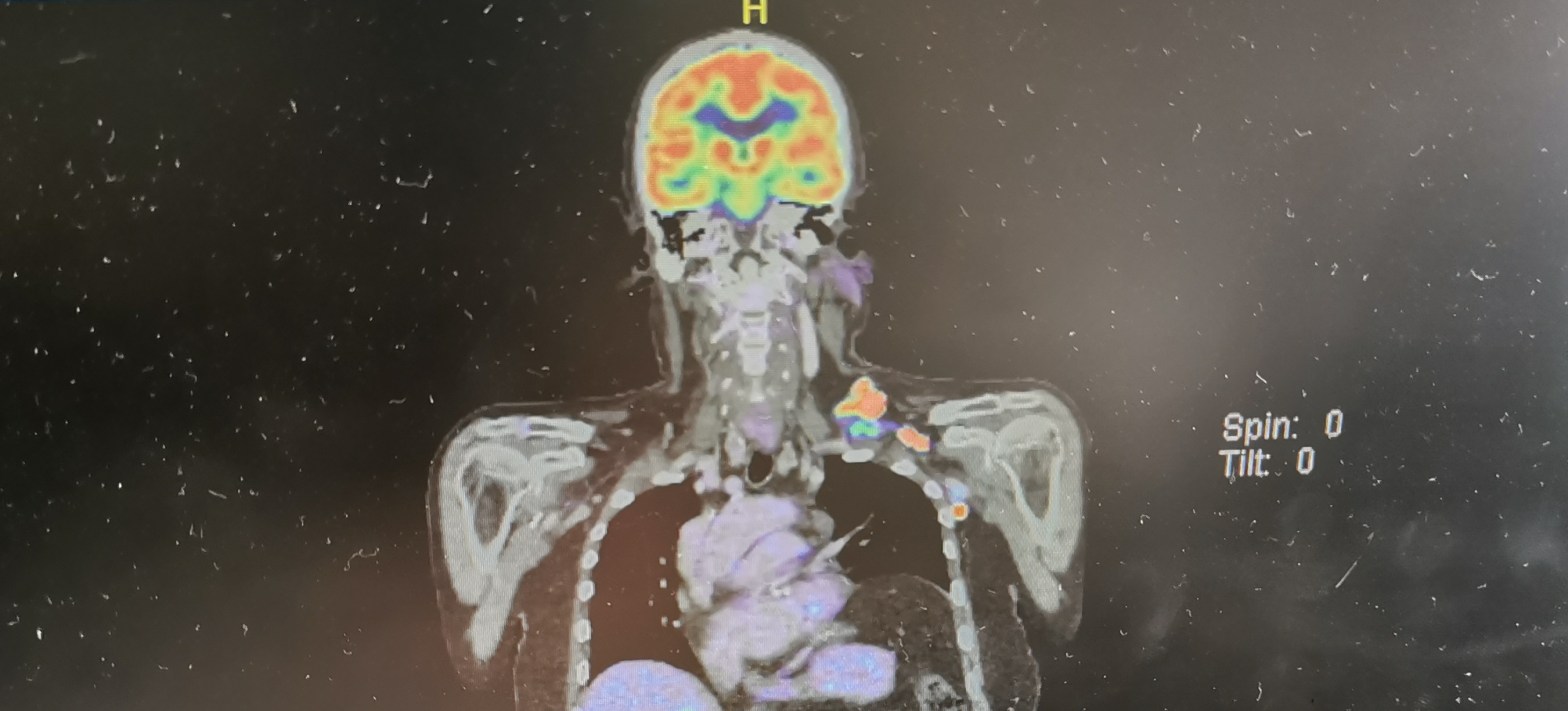

On the down side almost all of the tests I have just completed would in theory have to be repeated. Even the PET scan at a cost of around $3000 as the results of the previous scan belong to the previous trial. They would try and get this approved by the new trial but I should prepare myself for another PET scan. Before I left the hospital all of the blood tests were repeated along with another three ECG tests. I would say what a huge waste of money since I have already done these but the drug company is paying for the results, and they have plenty of money.

If I do have to have another PET scan it will be fascinating to see any changes in my enlarged nodes over such a short period. Since my disease has now transformed to the faster growing DLBCL I can almost feel the lump growing and it’s certainly becoming more prominent.